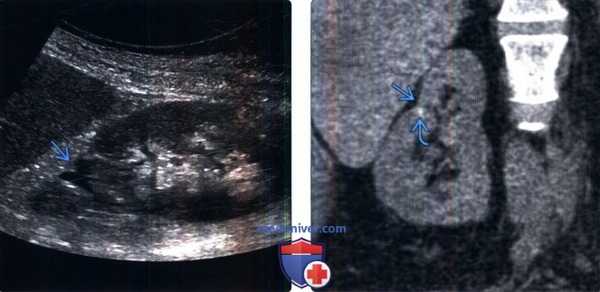

(Слева) УЗИ, продольная плоскость сканирования, правая почка: глубокий кортикальный рубец, ассоциированный с деформированной и расширенной чашечкой в верхнем полюсе.

(Справа) Бесконтрастная КТ, коронарная проекция: у данного пациента обнаружен кортикальный рубец в верхнем полюсе правой почки, ассоциированный с кальцификацией небольших размеров. При хроническом пиелонефрите рубцы обычно локализуются на полюсах почки (чаще на верхних).